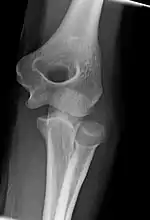

The elbow undergoes dynamic development of ossification centers through infancy and adolescence, with the order of both the appearance and fusion of the apophyseal growth centers being crucial in assessment of the pediatric elbow on radiograph, in order to distinguish a traumatic fracture or apophyseal separation from normal development. The order of appearance can be understood by the mnemonic CRITOE, referring to the capitellum, radial head, internal epicondyle, trochlea, olecranon, and external epicondyle at ages 1, 3, 5, 7, 9 and 11 years. These apophyseal centers then fuse during adolescence, with the internal epicondyle and olecranon fusing last. The ages of fusion are more variable than ossification, but normally occur at 13, 15, 17, 13, 16 and 13 years, respectively.[16] In addition, the presence of a joint effusion can be inferenced by the presence of the fat pad sign, a structure that is normally physiologically present, but pathologic when elevated by fluid, and always pathologic when posterior.[17]

Fractures

There are three bones at the elbow joint, and any combination of these bones may be involved in a fracture of the elbow. Patients who are able to fully extend their arm at the elbow are unlikely to have a fracture (98% certainty) and an X-ray is not required as long as an olecranon fracture is ruled out.[23] Acute fractures may not be easily visible on X-ray.

Elbow arthritis is usually seen in individuals with rheumatoid arthritis or after fractures that involve the joint itself. When the damage to the joint is severe, fascial arthroplasty or elbow joint replacement may be considered.[26]